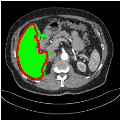

3.3 Results and Discussion

Our primary findings comparing the proposed model to baseline fully-supervised models when segmenting the liver from the LiTS dataset are reported in Table 1. The reported results demonstrate that our SAM-Mix model consistently achieves higher Dice scores compared to the fully supervised baselines as well as the two-stage SAM-PP method. Against U-Net, the best-performing fully supervised method, the SAM-Mix variant trained on 50 segmentation labeled slices (SAM-Mix-50), achieves a Dice score improvement of 5.9%. In terms of Hausdorff distance, while the fully-supervised baselines do slightly outperform SAM-Mix-5 and SAM-Mix-100, SAM-Mix-50 does achieve a lower Hausdorff distance by 22.38%. Qualitative evaluation as shown in Figs. 3 further affirms the superiority of SAM-Mix over baseline and existing fully-supervised methods as well as the two-stage SAM-PP variants. Furthermore, the boxplot visualization in Fig. 2 showcases consistently improved performance by SAM-Mix outperforming all the fully supervised and semi-supervised methods.

![]() |

| U-Net | nnU-Net | TransU-Net | SAM-PP-0 | SAM-PP-5 |

| SAM-PP-50 | SAM-PP-100 | SAM-Mix-5 | SAM-Mix-50 | SAM-Mix-100 |